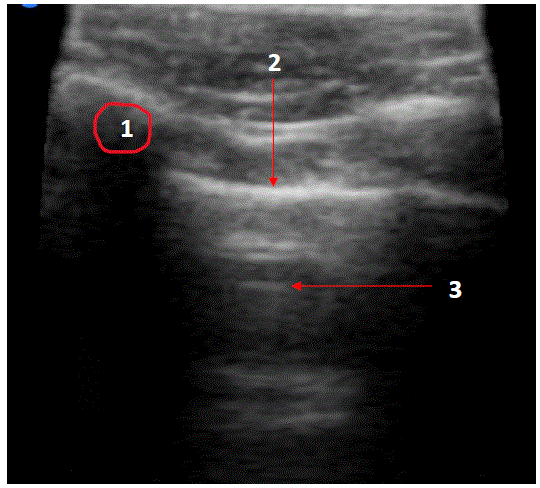

Atualmente a ultrassonografia está sendo utilizada com maior frequência para auxiliar no diagnóstico e procedimentos invasivos do tórax. Assinale a alternativa que contempla as estruturas corretamente identificadas na imagem abaixo obtida pelo ultrassom do tórax (parede torácica e espaço pleural).